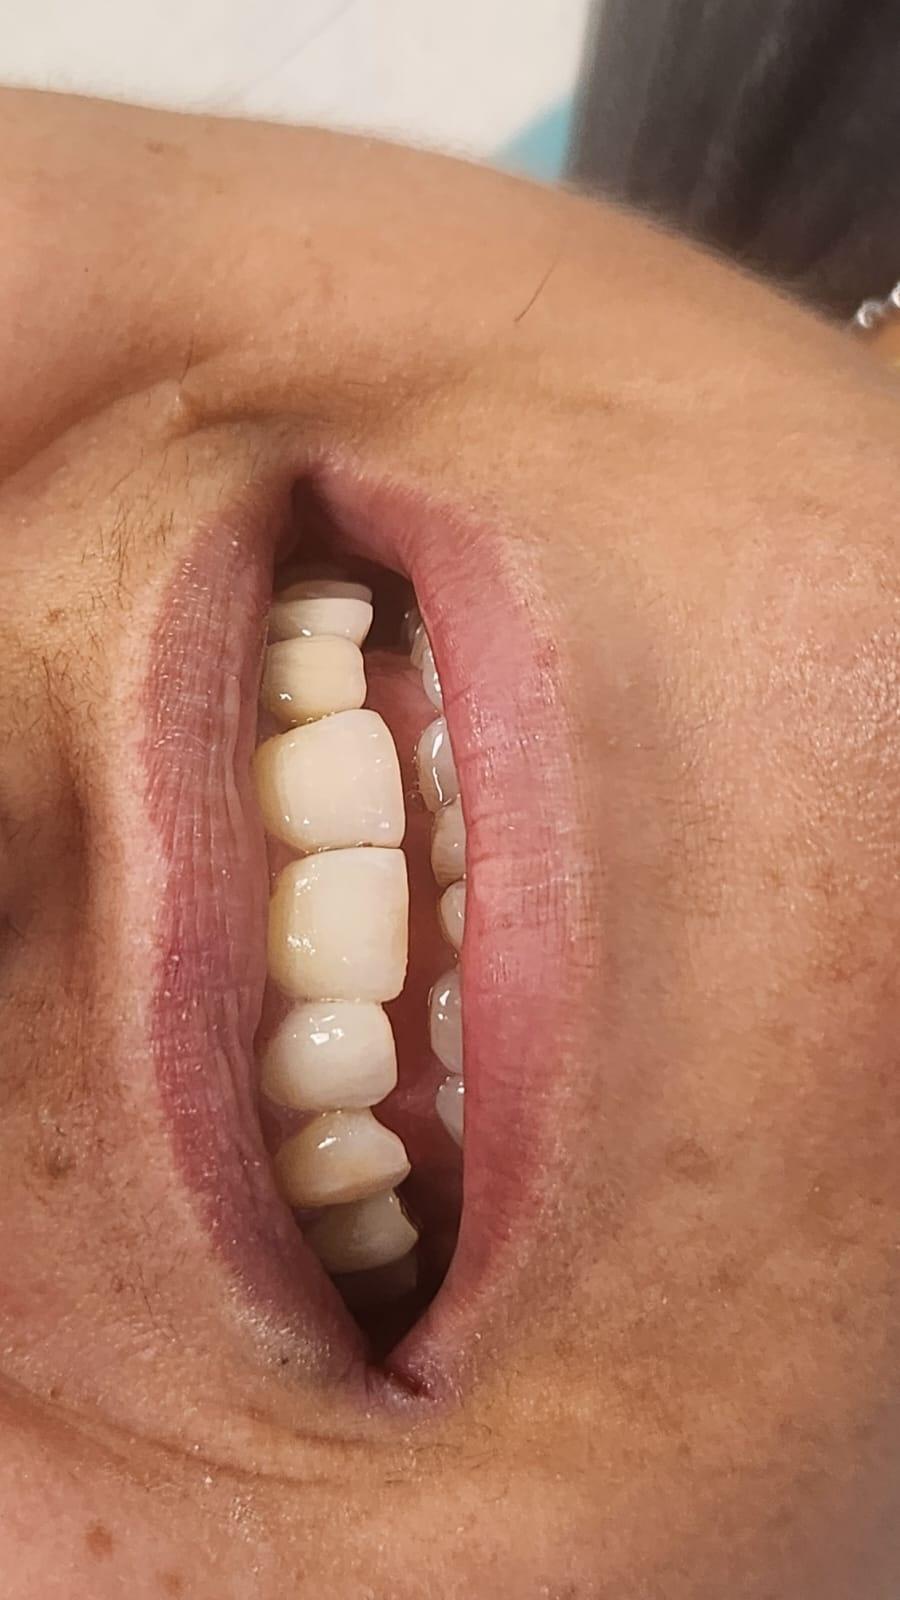

Clinica LUY ESTHETIC ART defineste parodontoza ca fiind rezultatul direct al placii dentare, care se depune pe suprafata dintilor, dar si in apropiere de marginea gingivala. Aceasta boala duce la pierderea dintilor, chiar daca ei sunt aparent sanatosi si nu prezinta carii. Edentatiile, afecteaza vorbirea, aspectul, dar si capacitatea de a mesteca.

Boala parodontala are un caracter progresiv. Pentru cazurile mai grave, recomandam tratamentul parodontal chirurgical rezectiv sau regenerativ.

– retractii gingivale cu expunerea radacinilor dentare;